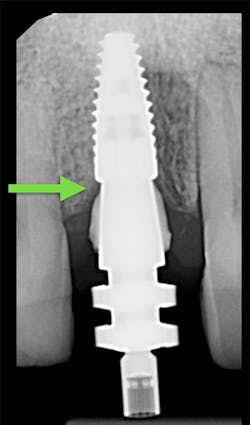

1. Place your open-tray impression coping on the implant you are planning to impress. Confirm its complete seating with a radiograph (figure 4). There should not be a space at the junction of the implant and impression coping.